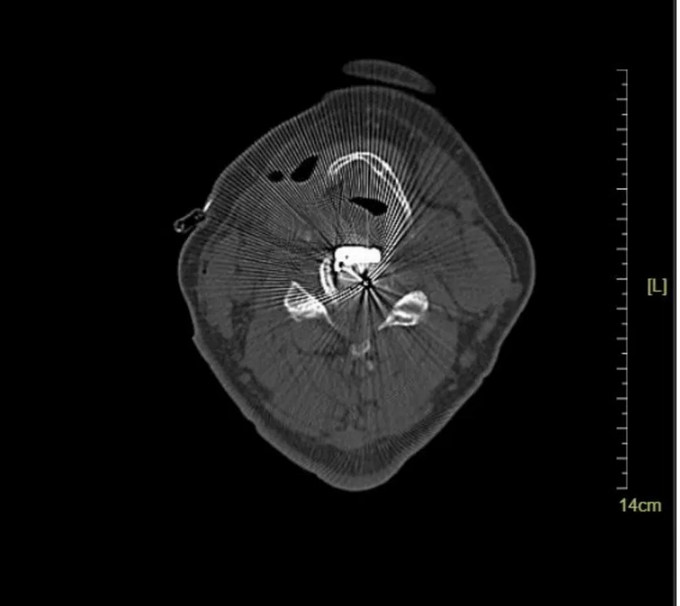

頸椎CT橫斷位 可以看到明顯突出的骨贅

頸椎MRI橫斷位